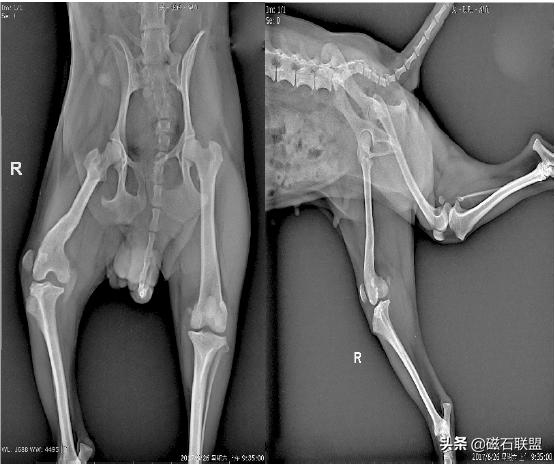

★手术方案:

对于滑车沟未变浅、胫骨及股骨未发生畸形者:可将脱位对侧的韧带重叠缝合,以紧缩关节囊,使髌骨复位。

对于滑车沟变浅者:应进行滑车再造成形术。对胫骨嵴生长内旋者,可将胫骨嵴移向外移动1 cm~2 cm,并用1 枚~2 枚骨针与手术钢丝固定。

★术后影像

泰迪犬后腿一瘸一拐的怎么回事,泰迪犬性格缺陷

★愈后:

手术后2小时即恢复清醒,一个月后基本恢复正常行走,取出钢针后恢复较为良好。